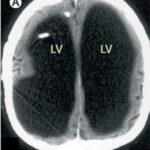

Na tomografia computadorizada, foi possível observar a massa grande e granulada no centro do corpo. Para tratar o problema, o homem precisou realizar um enema, que é quando um fluido é direcionado ao cólon para que os resíduos saiam naturalmente.